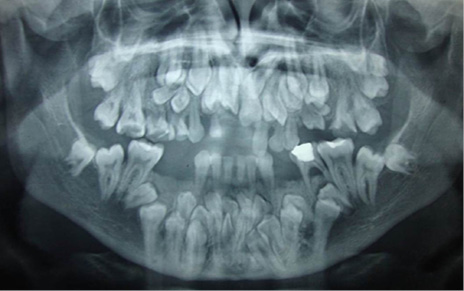

En el estudio imagenológico se observó en la radiografía de tórax, hipoplasia clavicular bilateral y tórax en forma de campana (Figura 2), en la radiografía panorámica se mostró la presencia de once dientes supernumerarios en el maxilar y nueve en la mandíbula (Figura 3), en la radiografía lateral cráneo se observó presencia de huesos wormianos landoideos (Figura 4); en la radiografía carpal se observó longitud simétrica de las falanges y sin alteraciones (Figura 5), de acuerdo con los hallazgos encontrados en el examen físico y la evaluación radiológica, se realizó la impresión diagnóstica de displasia cleidocraneal.

Autores como Paul et al, en 2015 y Forronato et al, en 2009, afirmaron que la radiografía periapical, panorámica, tomografía computarizada y la radiografía de cráneo son herramientas muy útiles para el diagnóstico bucal de la DCC, ya que permiten observar características consideradas patognomónicas para el diagnóstico del síndrome como los múltiples dientes supernumerarios, dientes retenidos y retraso en la osificación de las suturas craneales suturas [1,12]; coincidiendo con el presente caso en el cual el hallazgo radiográfico de alerta encontrado en la ortopantomografía fue la presencia de múltiples supernumerarios localizados en el maxilar y la mandíbula.